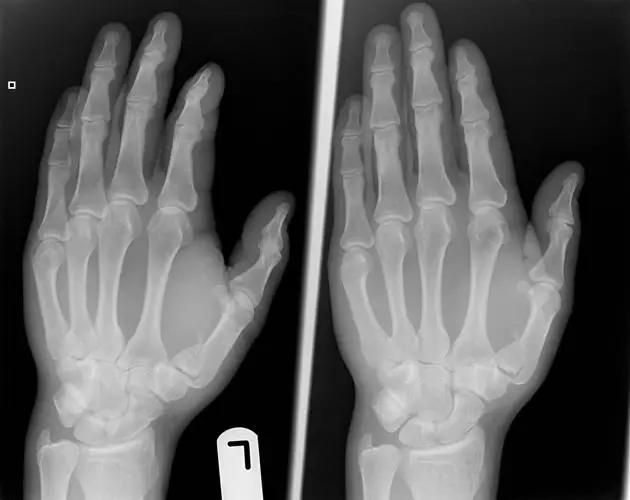

手腕部骨折

1. Barton 骨折

桡骨远端有移位的、不稳定的且经关节的桡骨远端骨折。可向掌侧也可向背侧移位。

6. Bennett 骨折

第 1 掌骨基底的斜形骨折,掌骨近端形成轴向移位,掌侧边缘形成三角形的骨碎片。

7. Boxer's 骨折

第 5 掌骨颈骨折伴有掌骨头向掌侧移位。

8. Mallet Finger/Baseball finger

即锤状指。远节指间关节的屈曲畸形,是由附着远节指骨伸肌腱分离引起,也可由伸肌腱的直接损伤继发引起。或由远节指骨撕裂性骨折引起肌腱嵌入骨折端引起。

9. Essex-Lopresti 骨折

是桡骨头骨折伴有下尺桡关节脱位,导致骨间膜损伤,桡骨短缩。此种损伤,桡骨头骨折的诊断往往是明确的,容易忽视的是下尺桡关节脱位,特别是早期,下尺桡关节的症状不明显,X 线表示也不明显。

Essex-Lopresti 损伤。前后位(A)和侧位(B)示桡骨头关节内骨折(白色实线箭头);(C~E)伤后 1 个月复诊,患者诉腕关节疼痛,X 线(C,D)发现下尺桡关节脱位,(E)CT 进一步证实损伤的存在 (来源:Radiol Clin North Am. 2015 Jul;53(4):717-36)

10. Rolando 骨折

第一掌骨基底的 T 或 Y 型粉碎性骨折,可伴有关节半脱位。

11. Buttonhole deformity/Boutonnière deformity(纽扣畸形)

伸肌腱的中央腱束断裂,使近侧指间关节突出于侧束指间,表现为近侧指间关节屈曲,远侧指间关节过伸畸形。多发生于类风湿性关节炎后畸形。